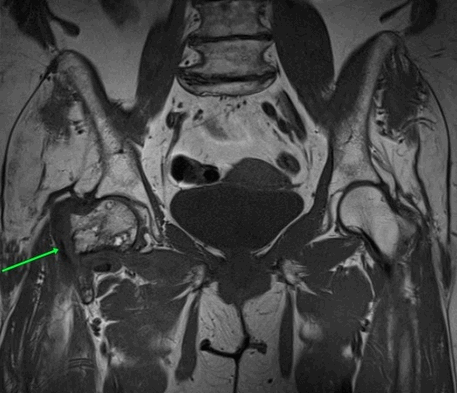

МРТ пояснично-крестцового отдела позвоночника. На Т2-ВИ в сагиттальной плоскости определяется компрессионный перелом L1 позвонка на фоне остеопороза.

МРТ покажет изменение формы позвонка, линию перелома, дефекты костной замыкательной пластины. Может меняться высота между позвонками. Если к перелому привела слабость костной ткани, на снимках кость выглядит более светлой из-за снижения содержания солей кальция между костными трабекулами.

Компрессионный перелом виден на рентгене при достаточной степени деформации позвонка, хорошо визуализируется на КТ во всех случаях. МРТ выгодно отличается тем, что показывает свежий перелом. Это определяет тактику лечения – максимально щадящий режим для спины, иммобилизация корсетом. Также он выявляет сопутствующую патологию дисков, грыжу, дегенеративные и воспалительные болезни позвоночника, суставов, спинного мозга и его оболочек, нервов, сосудов.